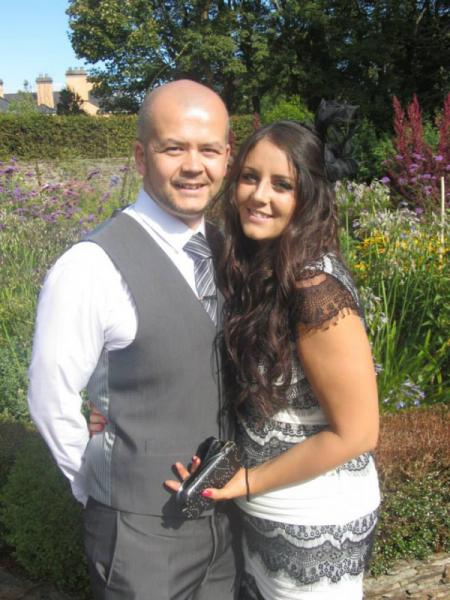

Michelle e Ross Hui de Newbridge (Irlanda) estão muito felizes. Eles já são pais de duas crianças e estão prestes a aumentar a família, já que Michelle está grávida novamente. Durante 6 semanas e 2 dias, ela carrega o bebê na barriga. Mas, de repente, ela sente uma dor aguda no caminho para o trabalho.

Pouco tempo depois ela vê sangue nas suas calças. A mulher de 31 anos corre para o hospital com seu marido, onde seus piores temores são confirmados: um check-up completo mostra que ela perdeu o bebê. Michelle e Ross ficam arrasados.

Os médicos dão a Michelle dois comprimidos que são usados normalmente para provocar abortos. Neste caso, a função do remédio é “limpar” o útero, ajudando a prevenir infecções. A mãe confia nos médicos e engole as pílulas. Depois de uma noite no hospital, ela está autorizada a ir embora.

Em casa, ela recebe a visita de amigos e afoga suas mágoas numa garrafa de vinho. Após alguns dias, Michelle precisa fazer outro teste de gravidez, para checar se existem quaisquer sinais residuais de uma gestação. Como o resultado foi positivo, 10 dias depois ela volta ao hospital para se submeter a uma raspagem de útero. Mas o que acontece em seguida é inacreditável!

Quando os médicos do Hospital Rotunda, em Dublin, analisam o útero de Michelle uma última vez antes de fazer a raspagem, eles escutam o batimento cardíaco inconfundível de outro ser! Michelle está grávida, apesar de seu aborto. O que aconteceu foi que ela estava originalmente grávida de gêmeos, mas um deles não sobreviveu. O segundo bebê conseguiu ficar vivo, apesar dos médicos não saberem como isso foi possível!

“O médico saiu e voltou com um colega mais experiente, que repetiu o exame e, em seguida, disse: ‘Você não acreditar, mas nós encontramos um batimento cardíaco‘ Essa foi a melhor sensação que eu já tive na vida“, diz Michelle. No final, a bebê Megan nasceu saudável e surpreendeu os médicos e seus pais.

Ninguém sabe se algum outro caso, semelhante a este, já aconteceu. Hoje com 18 meses, abebê está saudável e é o orgulho de seus pais e de seus irmãos, Ma (4) e Noah (2). Um outro mistério é que ninguém sabe como foi possível que Megan não tenha aparecido nos primeiros exames. Os médicos dizem que a menina ficou escondida no ultrassom, encoberta por sangue e outros fluidos residuais do aborto.